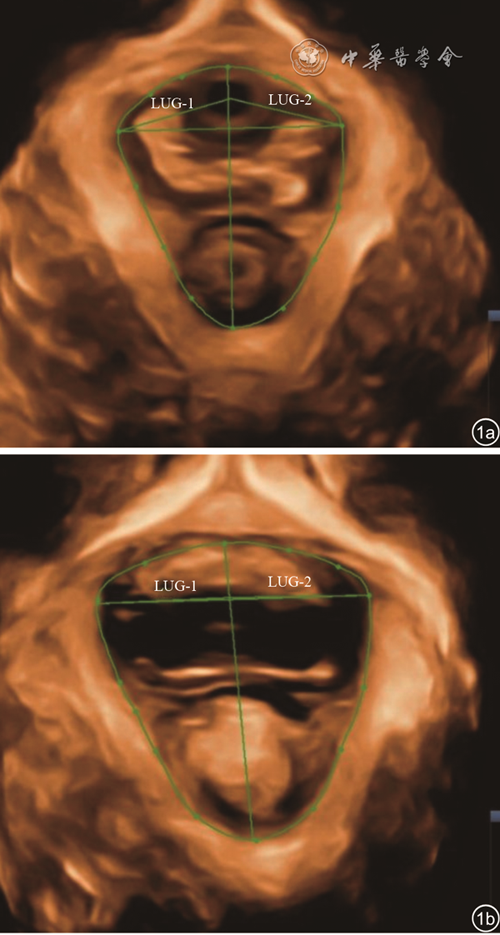

二、各组间静息状态及最大Valsalva状态下LH面积比较